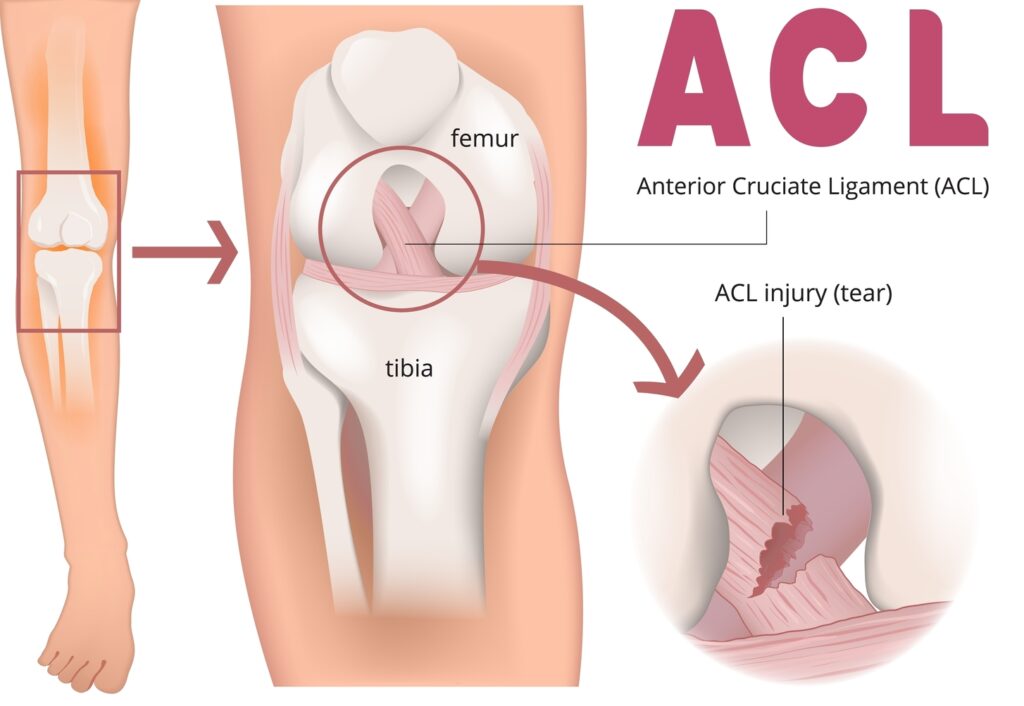

Ruptura ligamentului încrucișat anterior

Ruptura de ligament încrucișat anterior reprezintă una dintre cele mai frecvente leziuni traumatice ale genunchiului, în special la sportivi.

Poate fi parțială (câteva fibre rupte, dar cu stabilitate păstrată) sau completă (ligamentul este întrerupt total). În lipsa unei reconstrucții, ruptura completă determină instabilitate articulară și, în timp, poate favoriza deteriorarea meniscurilor și apariția artrozei.